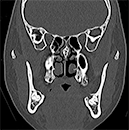

図❸ 右下智歯部に骨の異常所見はあきらかではなかった

画像所見:パノラマX線写真とCT画像で顎骨ならびに歯に異常所見は認めなかった(図❷❸)。